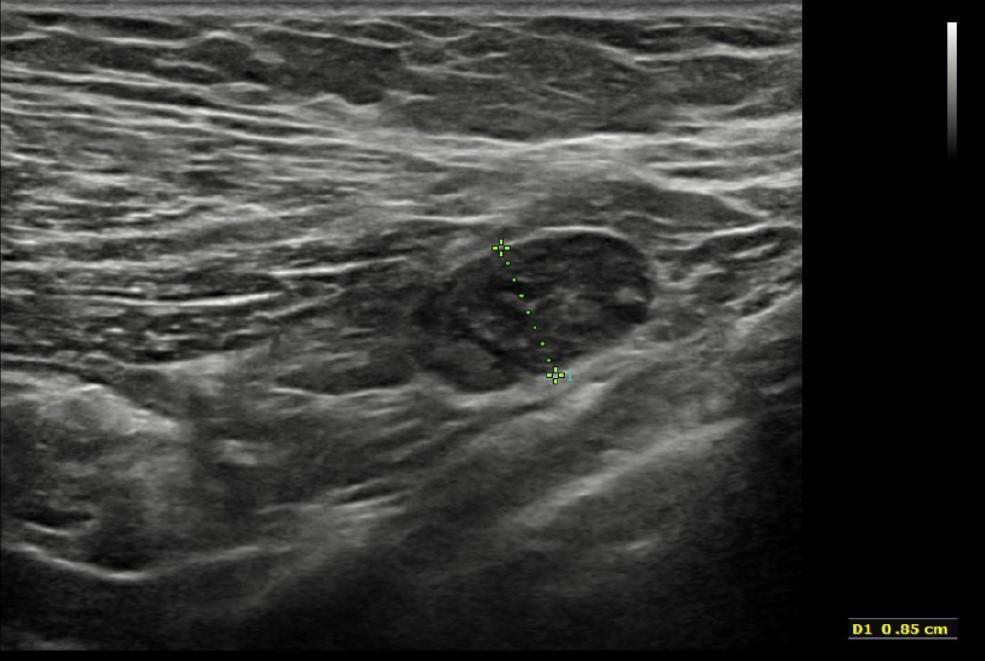

右侧腋窝超声检查可见一个边界清晰的复杂异质性肿块,内部可见小囊性成分以及脂肪回声区域(图8、9、10)。针对这些腋下肿块,建议进一步活检评估。